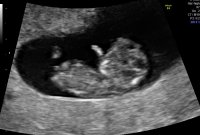

Lille bamsemums har nå blitt en minibaby ❤️ 10 uker i dag og alt ser fortsatt helt fint ut og vokser akkurat som hen skal :)